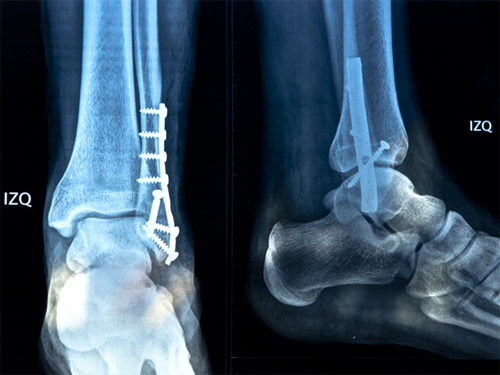

La radiografía luego de la intervención quirúrgica

La administración del espada hidrocálido ha compartido a los medios la imagen con la radiografía que le fue tomada tras la intervención quirúrgica, y que se anexa a esta nota, en la que se aprecia la placa modelada atornillada interfragmentada que le fue colocada en la zona de la fractura.